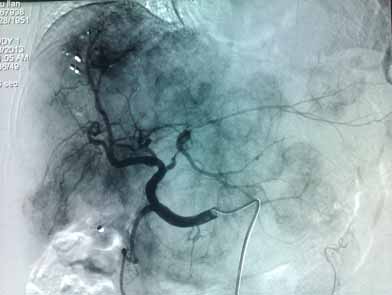

肝动脉分支血管增多、增粗,实质期肝脏可见多发大小不等结节状肿瘤染色

化疗栓塞后,结节状肿瘤染色消失,可见多发碘油沉积影